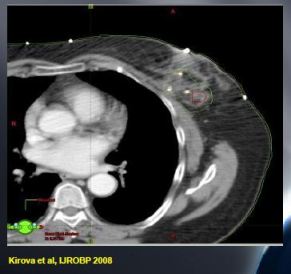

Kontúrovanie boostu CTV-PTV, literatura

Klinicky definované lôžko vs klipy

Neadekvátna pozícia klinicky definovaného lôžka:

- 9/24 (37%) Denham&Carter 1988

- 19/35 (54%) Bedwinek 1993

- 34/50 (68%) Harrington et al 1996

Klinicky definované lôžko vs CT definované lôžko (Messer et al, R&O 1997):

- 34/45 (75%) zmena energie elektrónov

- 12/45 (26%) zmena veľkosti poľa

CTV by malo byť definované na základe:

- Predoperačného klinického vyšetrenia

- Predoperačných zobrazovacích metód (NMG, USG)

- Zmeny viditeľné na CT: jazva, seróm, klipy

Definícia boost CTV

Veľkosť CTV a PTV lemov

- CTV Lemy

- Holland et al: >2cm

- Vinci et al 2004: 1cm

- Young boost trial: 1,5cm

- PTV lemy:

- Literatura: variácie od 0,5-1cm

- Young boost trial: 0,5cm

Doporučenia pre delineáciu CTV a PTV boostu

- CTV boost:

- Tkanivo prsníka okolo tumoru (před lumpektómiou) + lem 1,5cm

- Zabrať do objemu klipy a vnútornú jazvu!!!

- Alebo: kavita po excízii (seróm) + 1,5cm

- PTV boost:

- CTV + 0,5cm vo vrtkých smeroch (rátať s nepresnosˇami nastavenia, pohybom orgánov)

- V prípade elektrónového poľa nie je definovaný lem zo strany vstupu poľa